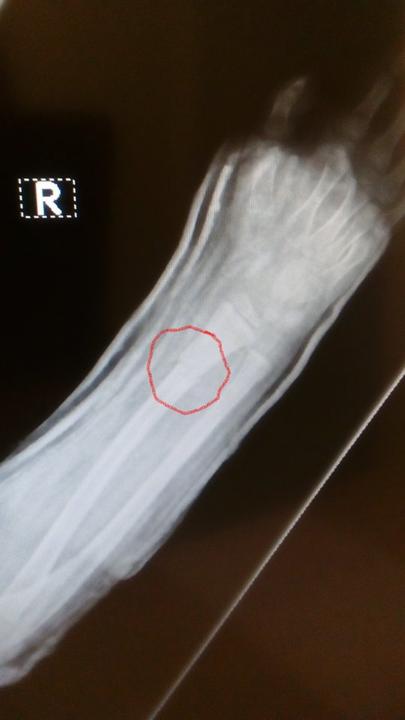

Neznáte prosím nějakého dobrého ortopeda, který se specializuje na děti? Klidně celá Morava. Začínáme být zoufalí...